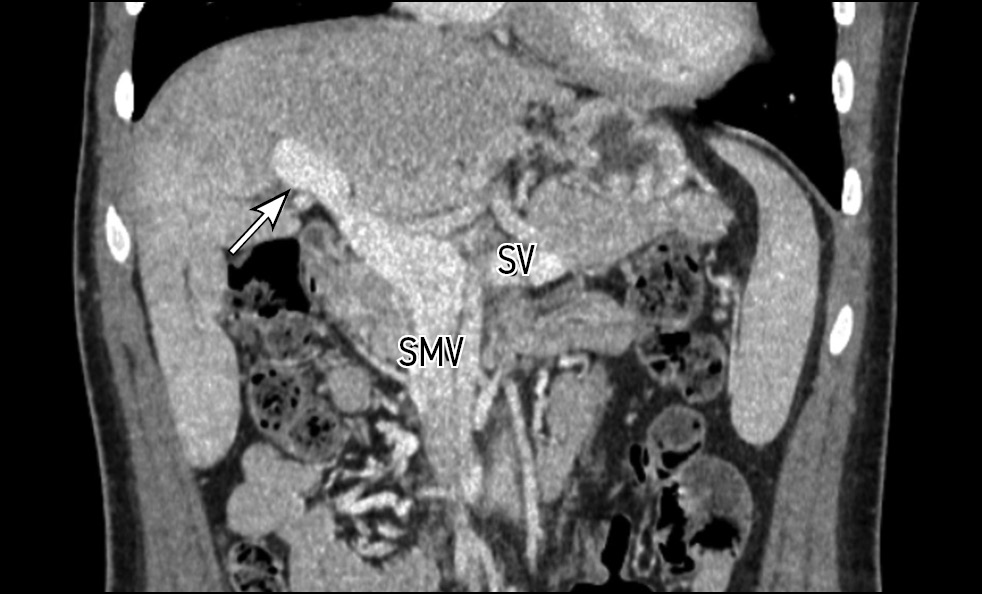

Contrast-enhanced abdominal computed tomography (CT) with multiplanar reconstruction revealed that the splenic (12 mm in diameter (Figure 1)) and superior mesenteric veins fused together, forming a portal vein conduit dilated to 28 mm in diameter (Figures 2 and 3), flowing directly into the inferior vena cava (IVC), bypassing the porta hepatis (Figure 4). Moreover, moderate liver and spleen enlargement and weak heterogeneous contrast enhancement of the liver parenchyma were noted. The findings were consistent with Abernethy malformation type Ib.

Fig. 3. Contrast-enhanced CT, portal phase, axial view. Portal vein conduit (white arrow).

Fig. 4. Contrast-enhanced CT, portal phase, coronal view. Portal vein conduit flowing directly into the IVC (white arrow), enlarged liver with heterogeneous parenchymal enhancement.